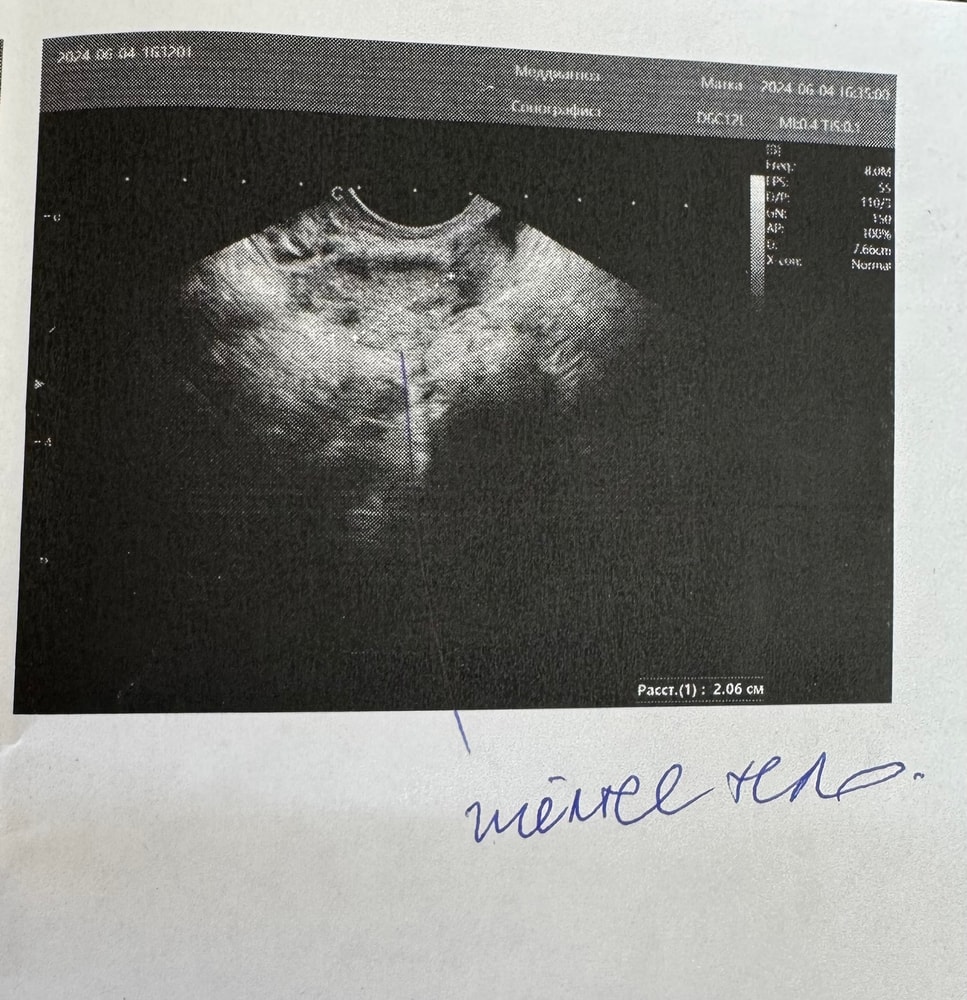

Желтое тело без классического кровотока

УЗИБыла на фолликулометрии днем на 15 дц, овуляция по ощущениям была в ночь с 14 на 15 дц. Узистка долго смотрела, потом увидела желтое тело 20 мм без классического кровотока. Правильно я понимаю, что кровоток виден на узи не сразу? При чем ЖТ в левом яичнике, а за последний год он ни разу не овулировал, всегда рабочий был правый, и собственно ничего не получалось. Похоже вообще на желтое тело (прикрепляю фото) или это вообще не оно?